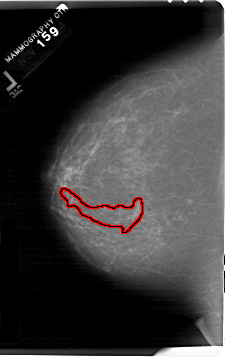

FILE: A_1202_1.LEFT_CC.OVERLAY

TOTAL_ABNORMALITIES 1

ABNORMALITY 1

LESION_TYPE CALCIFICATION TYPE PLEOMORPHIC DISTRIBUTION SEGMENTAL

ASSESSMENT 5

SUBTLETY 3

PATHOLOGY MALIGNANT

TOTAL_OUTLINES 1

BOUNDARY